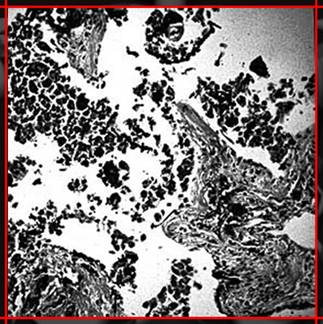

7-8 La doctora sitúa en la pantalla de luz la radiografía de los pulmones y la mira con una lupa. El trabajador observa atentamente desde detrás.

Voz en off Chica- El estudio radiológico del tórax. En función de los resultados se podrán hacer otras pruebas como una tomografía computada o una tomografía computada de alta resolución.

Voz en off Chica- Considerando el incremento del riesgo de sufrir cáncer de pulmón derivado de la exposición conjunta al amianto y al tabaco, es importante incluir este punto en los exámenes de salud.